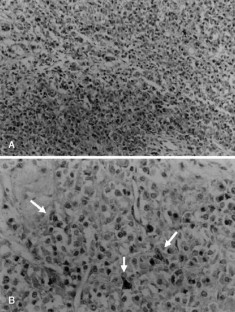

Fig. 4 A